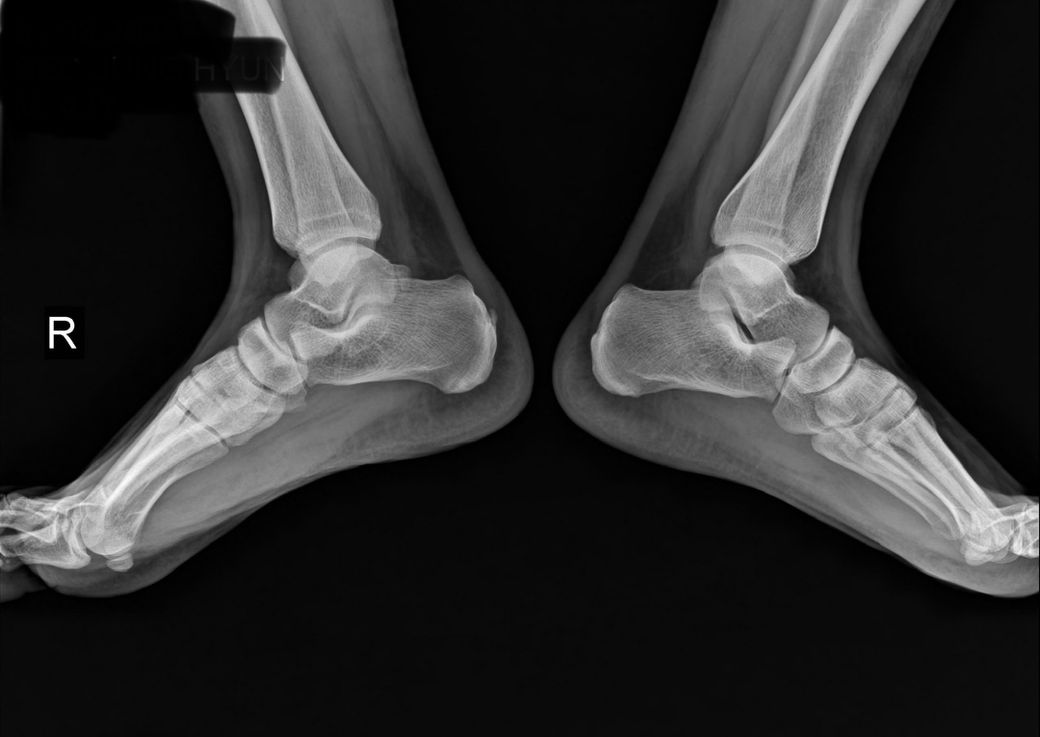

오른쪽 발 아킬레스건염이 계속 재발되서 병원 엑스레이 찍어보니 평발이라 발 뒷꿈치에 석회가 쌓여서 석회땜에 염증이 계속 생긴다고 프롤로주사로 석회를 제거하고 나머지 부분도 치료한다고 하는데 이렇게 치료하는게 효과가 있는지 궁금합니다.

• 1번 째 사진